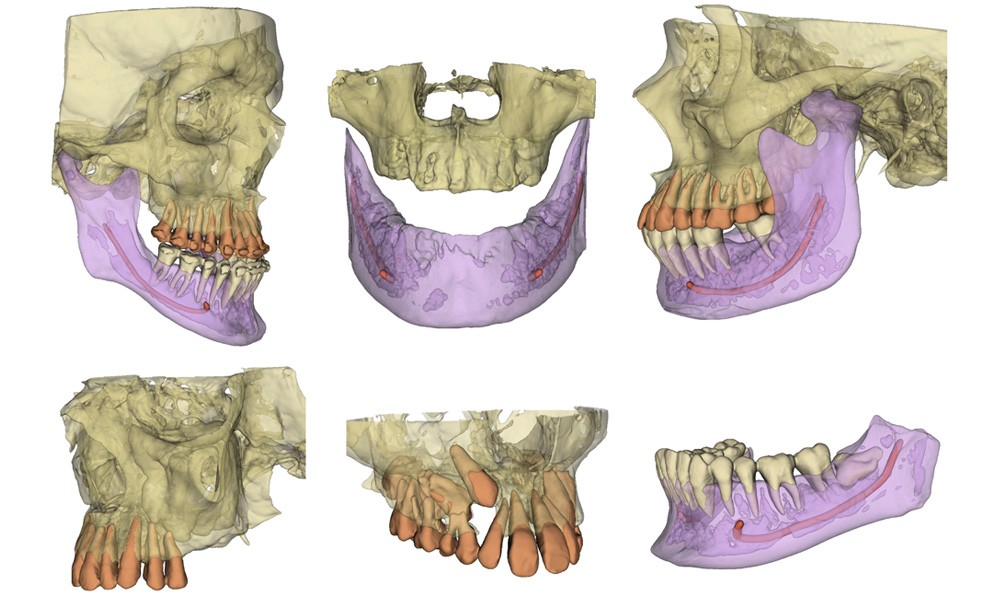

Nous avons alors recours à la segmentation de l’imagerie CBCT : cette méthode permet de « colorier » les éléments d’intérêt sur les différentes coupes de l’imagerie, pour reconstruire finement la situation tridimensionnelle (fig. 2). Les 3 incisives surnuméraires sont alors facilement objectivables. L’obstacle majeur à l’utilisation de cet outil en clinique est le temps nécessaire pour effectuer cette segmentation : à l’époque, il fallait plusieurs heures de « coloriage » manuel pour un seul CBCT [1] ! Ce temps de traitement constituait un frein majeur à l’adoption de cet outil en clinique, ce qui a constitué la motivation principale de notre travail.